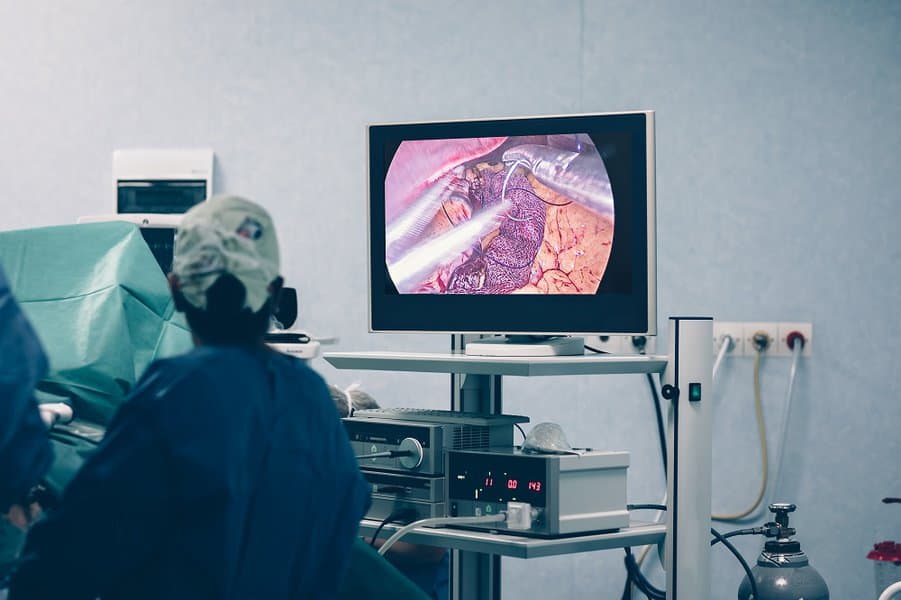

Cholecystectomy is another standard procedure that’s one of the most frequent operations in hospitals. A cholecystectomy treats gallstones and other conditions by removing the gallbladder. Furthermore, it treats gallbladder cancer, biliary colic, cholangitis, and gallstone pancreatitis. Despite being a common surgery, cholecystectomy is still a dangerous procedure.

In addition to a biliary injury, patients can suffer damage to the intestines, liver, and blood vessels. Several issues can arise from the surgery, such as a hernia, wound infection, and biliary injury. Depending on the situation, patients have two options for surgery: the open surgical technique or laparoscopically.